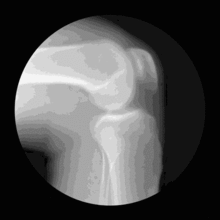

许多人认为,经常跑步易患退化性关节炎。不过,一项研究推翻了这样的论点。该研究发现,进行有规律跑步不仅不会增加患退化性关节炎的风险,反而还有助于预防退化性关节炎。美国贝勒医学院的研究人员分析了一项退化性关节炎研究数据,包括2683人。研究人员比较这些人的运动习惯后发现,无论年龄大小,只要进行有规律地跑步,出现膝盖疼痛的几率就会明显降低,且较不会产生退化性关节炎。

骨关节炎是关节炎症中最常见的一种,美国约翰霍普金斯大学医学院的研究发现,患有失眠症的膝盖骨关节炎患者与单纯只患有膝盖骨关节炎的患者相比,会感受到更多的疼痛且活动能力也较差。据研究作者在《Arthritis Care and Research》期刊中的描述,在患有失眠症的参与者中,同时患有膝盖骨关节炎的个体报告的睡眠中断较多,这些人的睡眠效率也较差。